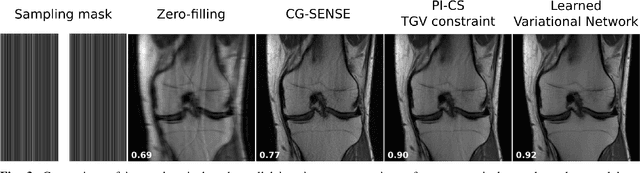

Abstract:Following the success of deep learning in a wide range of applications, neural network-based machine learning techniques have received interest as a means of accelerating magnetic resonance imaging (MRI). A number of ideas inspired by deep learning techniques from computer vision and image processing have been successfully applied to non-linear image reconstruction in the spirit of compressed sensing for both low dose computed tomography and accelerated MRI. The additional integration of multi-coil information to recover missing k-space lines in the MRI reconstruction process, is still studied less frequently, even though it is the de-facto standard for currently used accelerated MR acquisitions. This manuscript provides an overview of the recent machine learning approaches that have been proposed specifically for improving parallel imaging. A general background introduction to parallel MRI is given that is structured around the classical view of image space and k-space based methods. Both linear and non-linear methods are covered, followed by a discussion of recent efforts to further improve parallel imaging using machine learning, and specifically using artificial neural networks. Image-domain based techniques that introduce improved regularizers are covered as well as k-space based methods, where the focus is on better interpolation strategies using neural networks. Issues and open problems are discussed as well as recent efforts for producing open datasets and benchmarks for the community.